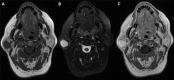

Hemangiomas account for 0.4-0.6% of all tumors of the parotid gland and most of them occur in children, nevertheless in adults hemangiomas are very rare. We report the case of a 62 year old woman with a mass in the parotid right tail associated with fluctuating swelling episodes unrelated to meals and with a slowly progressive growth. The provisional diagnosis was a pleomorphic adenoma, so a right superficial parotidectomy was performed. During surgery, the macroscopic appearance makes suspect a vascular lesion. The histopathological result was a cavernous hemangioma. The classic clinical presentation of a parotid hemangioma is an intraglandular mass associated or not with skin lesions characterized by reddish macules and/or papules, and a vibration or pulsation when palpating the parotid region. In imaging tests, phleboliths could be observed which are very suggestive of a hemangioma or a vascular malformation. In the absence of these signs, the diagnosis could be difficult, particularly in an adult due to its low prevalence, with about 50 cases reported worldwide. However a hemangioma should be considered in the differential diagnosis of parotid tumors in adults. Key words:Cavernous hemangioma, parotid gland, superficial parotidectomy, pleomorphic adenoma.